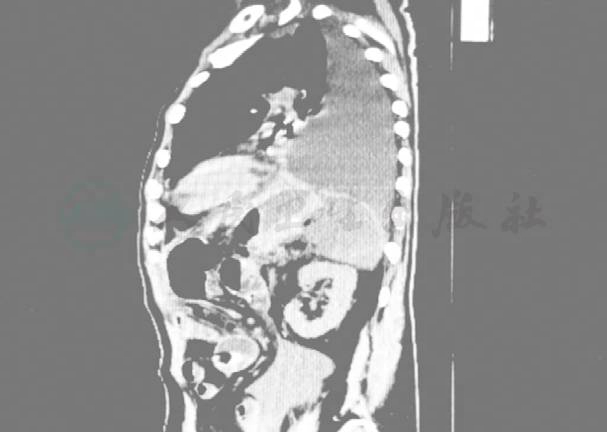

2015年3月1日(术后半个月)患者开始出现间断高热,肺部触诊语颤减弱,左下肺叩诊浊音,未闻及干湿性啰音;复查胸腹部CT提示:①双侧胸腔少量积液,左侧部分包裹(图3);②腹部、盆腔积液(图4)。行上消化道造影未见异常(图5)。考虑胸腔积液、膈下感染,3月1日、3月4日 B超引导下行胸腔、膈下穿刺置管引流,腹腔穿刺引出脓性液体(图6),行标本细菌培养+药敏提示:铜绿假单胞菌感染。查腹水淀粉酶:3364U/L。先后予亚胺培南、左氧氟沙星抗感染、引流管冲洗。

图5 消化道造影